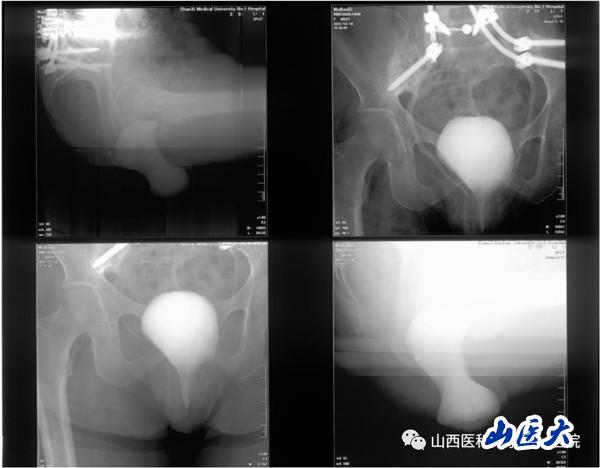

患者女性,62岁,盆腔脏器脱垂合并骶骨缺损,近年来辗转北京及省内各大医院寻求外科治疗,但均未能如愿。

会前,泌尿外科联合胃肠外科、妇科、疝与腹壁外科、整形科、康复科等科室组成的盆底MDT团队,对每一个病例进行了充分的评估及准备。讨论当天,由任力娟教授陪同申吉泓教授带领的专家团队,来到病房对患者进行了床旁查体及病史询问。此次研讨会亮点在于以“实战”为主,通过以术前病例讨论并制定手术方案、术中手术指导及交流的形式进行。术前与会专家与泌尿外科尿控及盆底疾病亚专业团队、胃肠外科、妇科等专家再次进行病例分析、讨论,以不同学科角度进行手术方案的对比,制定最终手术方案。手术于上午9时开始。术中,与会专家、泌尿外科尿控及盆底疾病亚专业团队、手术室护理团队、麻醉科医师团队精诚协作,互相配合。下午6时,伴随着最后一位手术患者麻醉苏醒,8台手术顺利结束。术中手术室护理团队及麻醉科医师团队的高效配合及无缝衔接,给在场的每一位专家留下了深刻的印象,以申吉泓教授为首的省外专家给予了高度评价及赞赏。